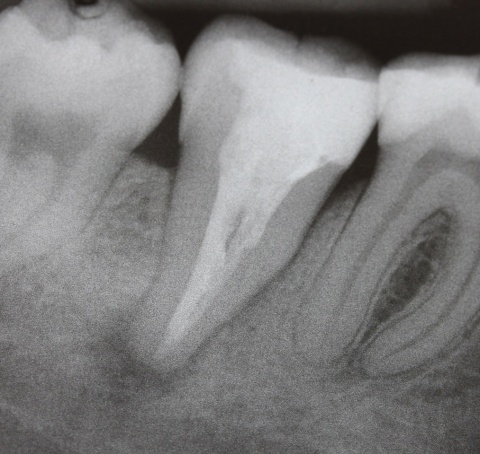

Ein nach Applikation des MTA angefertigtes Kontrollbild zeigt den suffizienten apikalen Verschluss der Konstriktion in einer Schichtstärke von etwa vier Millimeter (Abb. 2). Gleichzeitig wird in der Aufnahme die ausgedehnte Kanalstruktur des Zahnes 47 deutlich.

Im zweiten Schritt wurde durch plastisch erwärmte Guttapercha im Sinne der Back-Fill-Phase das Kanalsystem vollständig gefüllt und der Zahn anschließendadhäsiv verschlossen (Abb. 3). Zwölf Monate nach der Revisionsbehandlung ist die Patientin weiterhin beschwerdefrei und die Kontrollaufnahme zeigt den deutlichen Rückgang der apikalen Osteolyse (Abb. 4).